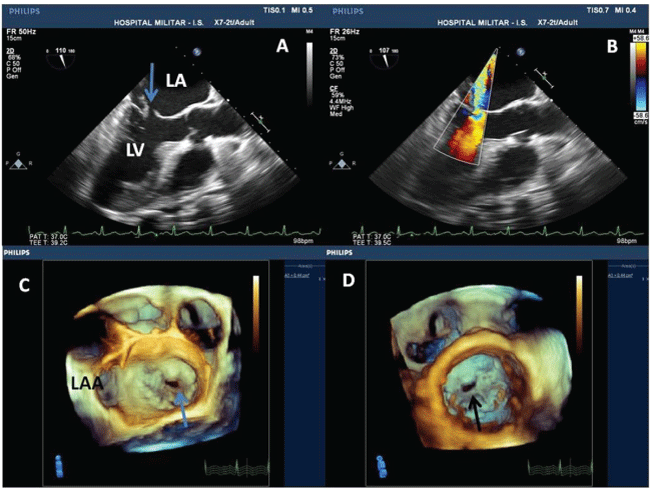

A 63-year-old man was referred to perform a transesophageal echocardiography (TEE) for suspicion of mitral endocarditis. The 2-Dimensional TEE showed a solution of continuity in the anterior leaflet of the mitral valve compatible with mitral perforation (Figure 1A). The Doppler color study revealed severe mitral regurgitant jet through the perforation (Figure 1B). The 3-Dimensional TEE confirmed perforation of the anterior mitral valve leaflet in the A2-A3 scallops (Figure 1C, and Figure 1D); vegetations were excluded. Perforation of mitral valve leaflets is a well known complication of infective endocartitis [1]. The incidence may be higher than whish had been reported in autopsy studies; around 8-20%. [1] 3-Dimensional TEE plays a key role in the characterization of valvular heart disease, especially, the mitral valve disease [2-4]. In spite of high quality of 2-Dimensional TEE, the 3-Dimensional TEE proved to be more accurate to characterize the localization of the anterior mitral leaflet perforation and to exclude mitral valve vegetations than the 2-Dimensional TEE [4,5]. It provide anatomical details of the mitral valve and precise localization of the perforation, which is very important for surgical planning because the en face view can simulate the view of the surgeons [6]. The present case illustrate the great accuracy of the real time 3-Dimensional TEE in the morphological analysis of mitral valve perforation.

Figure 1: (A) 2-Dimensional transesophageal echocardiography revealed contiguity solution of the anterior leaflet of the mitral valve; (B) Doppler color study showing severe mitral regurgitation through the perforation; (C and D) Real time 3-Dimensional transesophageal echocardiography revealing the anterior leaflet of the mitral valve perforation in A2-A3 scallops; "en face" view from the left atrium and the left ventricle respectively. LAA - Left Atrial Apenddage; LA - left atrium; Ao - Aorta; LV - left ventricle.